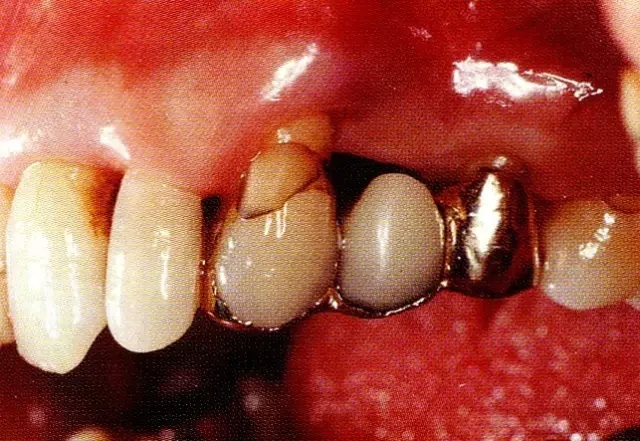

640.webp (13).jpg

▲圖8-8  再生療法12個月后,進(jìn)行再翻瓣,骨缺損部位可看到出現(xiàn)骨再生。牙齒和牙槽骨之間無法插入牙周探針,因而確認(rèn)臨床性支持組織形成了再生。